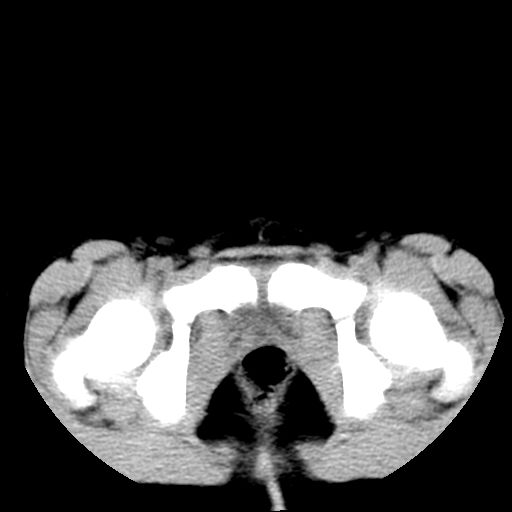

腹部好象未见异常。

腹部ct平扫未见明确异常

腹部ct平扫不能提示哪里有病变。